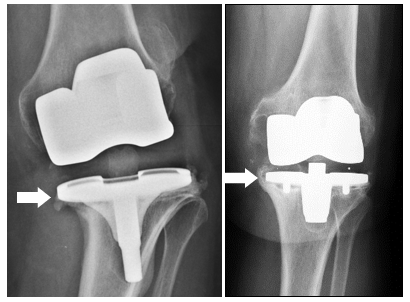

تشمل الأسباب الشائعة لاستبدال الركبة الاصطناعية، بالإضافة إلى العدوى، عدم الاستقرار أو الألم المستمر.

كجزء من عملية جديدة للركبة ،

عمليات الزرع الخاصة ضرورية لاستبدال الأربطة المعيبة (مع ما يسمى

بدلة مقترنة ) أو لبناء عيوب العظم (عن طريق زيادة أو استبدال العظام).